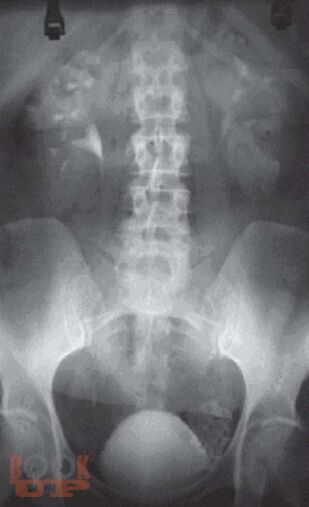

Монография посвящена применению лучевых методов исследования в ранней диагностике острого пиелонефрита. Систематизированы лучевые симптомы заболевания, на основании применения рентгенологического и ультрасонографического методов, а также метода компьютерной томографии. Представлена лучевая семиотика различных форм гнойного пиелонефрита (апостематоз, карбункул, абсцесс). Показана динамика изменений воспалительного процесса в паренхиме почек в процессе лечения. Данное практическое руководство будет интересно врачам лучевым диагностам, терапевтам, урологам, хирургам, а также студентам медицинских вузов.